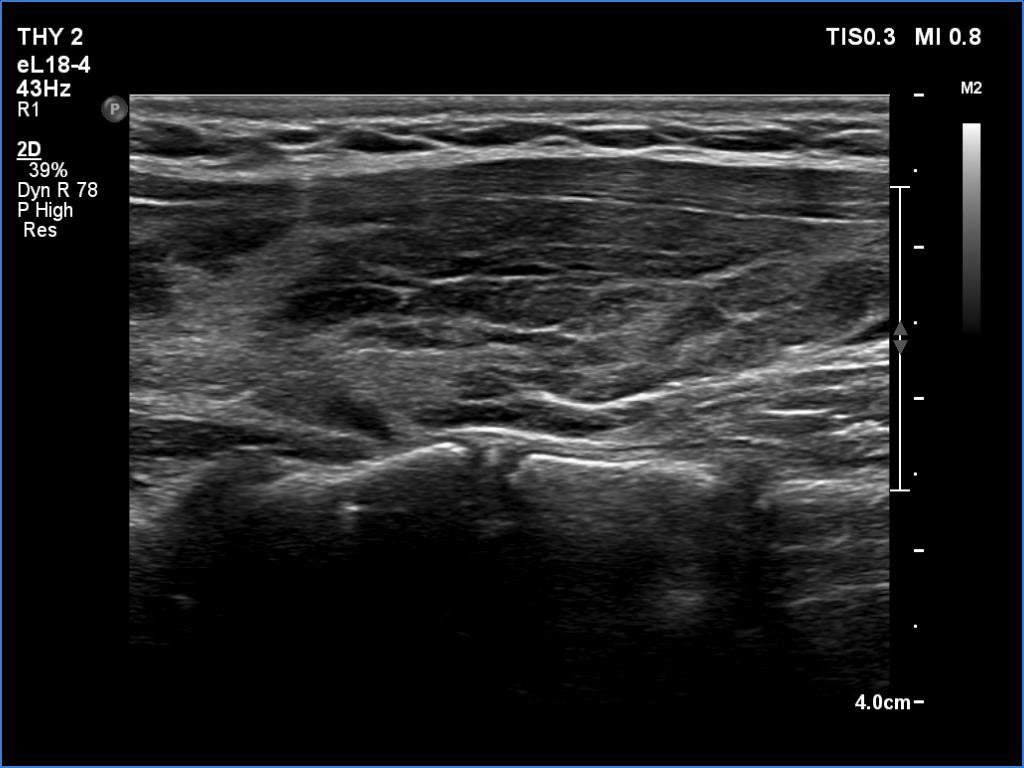

Lymphocytic thyroiditis - case 751

Left lobe

Focal form of lymphocytic thyroiditis is presented. The thyroid has numerous discrete, hypoechoic lesions which correspond to more active foci of thyroiditis. The interpretation of this pattern should not cause concern - these areas are not pathological nodules. The discrete lesions have non-regular, partly clearly lobulated or spiculated margins.